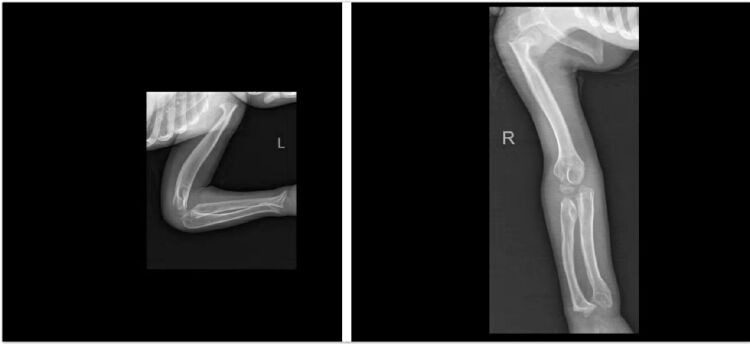

陈纯教授仔细询问了小昊的病史和家族史,做了细致的体格检查,发现小昊不仅仅是四肢畸形、步态异常和智力障碍,还存在角膜混浊的现象。随后在陈纯教授的指导下,凤庆县人民医院儿科医生给小昊进行了全身骨骼X线摄片,结果让人大吃一惊——小昊的骨头和关节形状异于常人,存在脊柱椎体形态异常,生理曲度异常,骨质密度增高,关节对位不正常,关节变形,眼眶、蝶鞍边缘骨质硬化等问题。

▲  小昊左臂与右腿X光片

根据四肢骨质发育异常、外貌特点、智力障碍和角膜混浊的情况,陈纯教授很快将疑诊的范围缩小到遗传代谢病,尤其是粘多糖病。